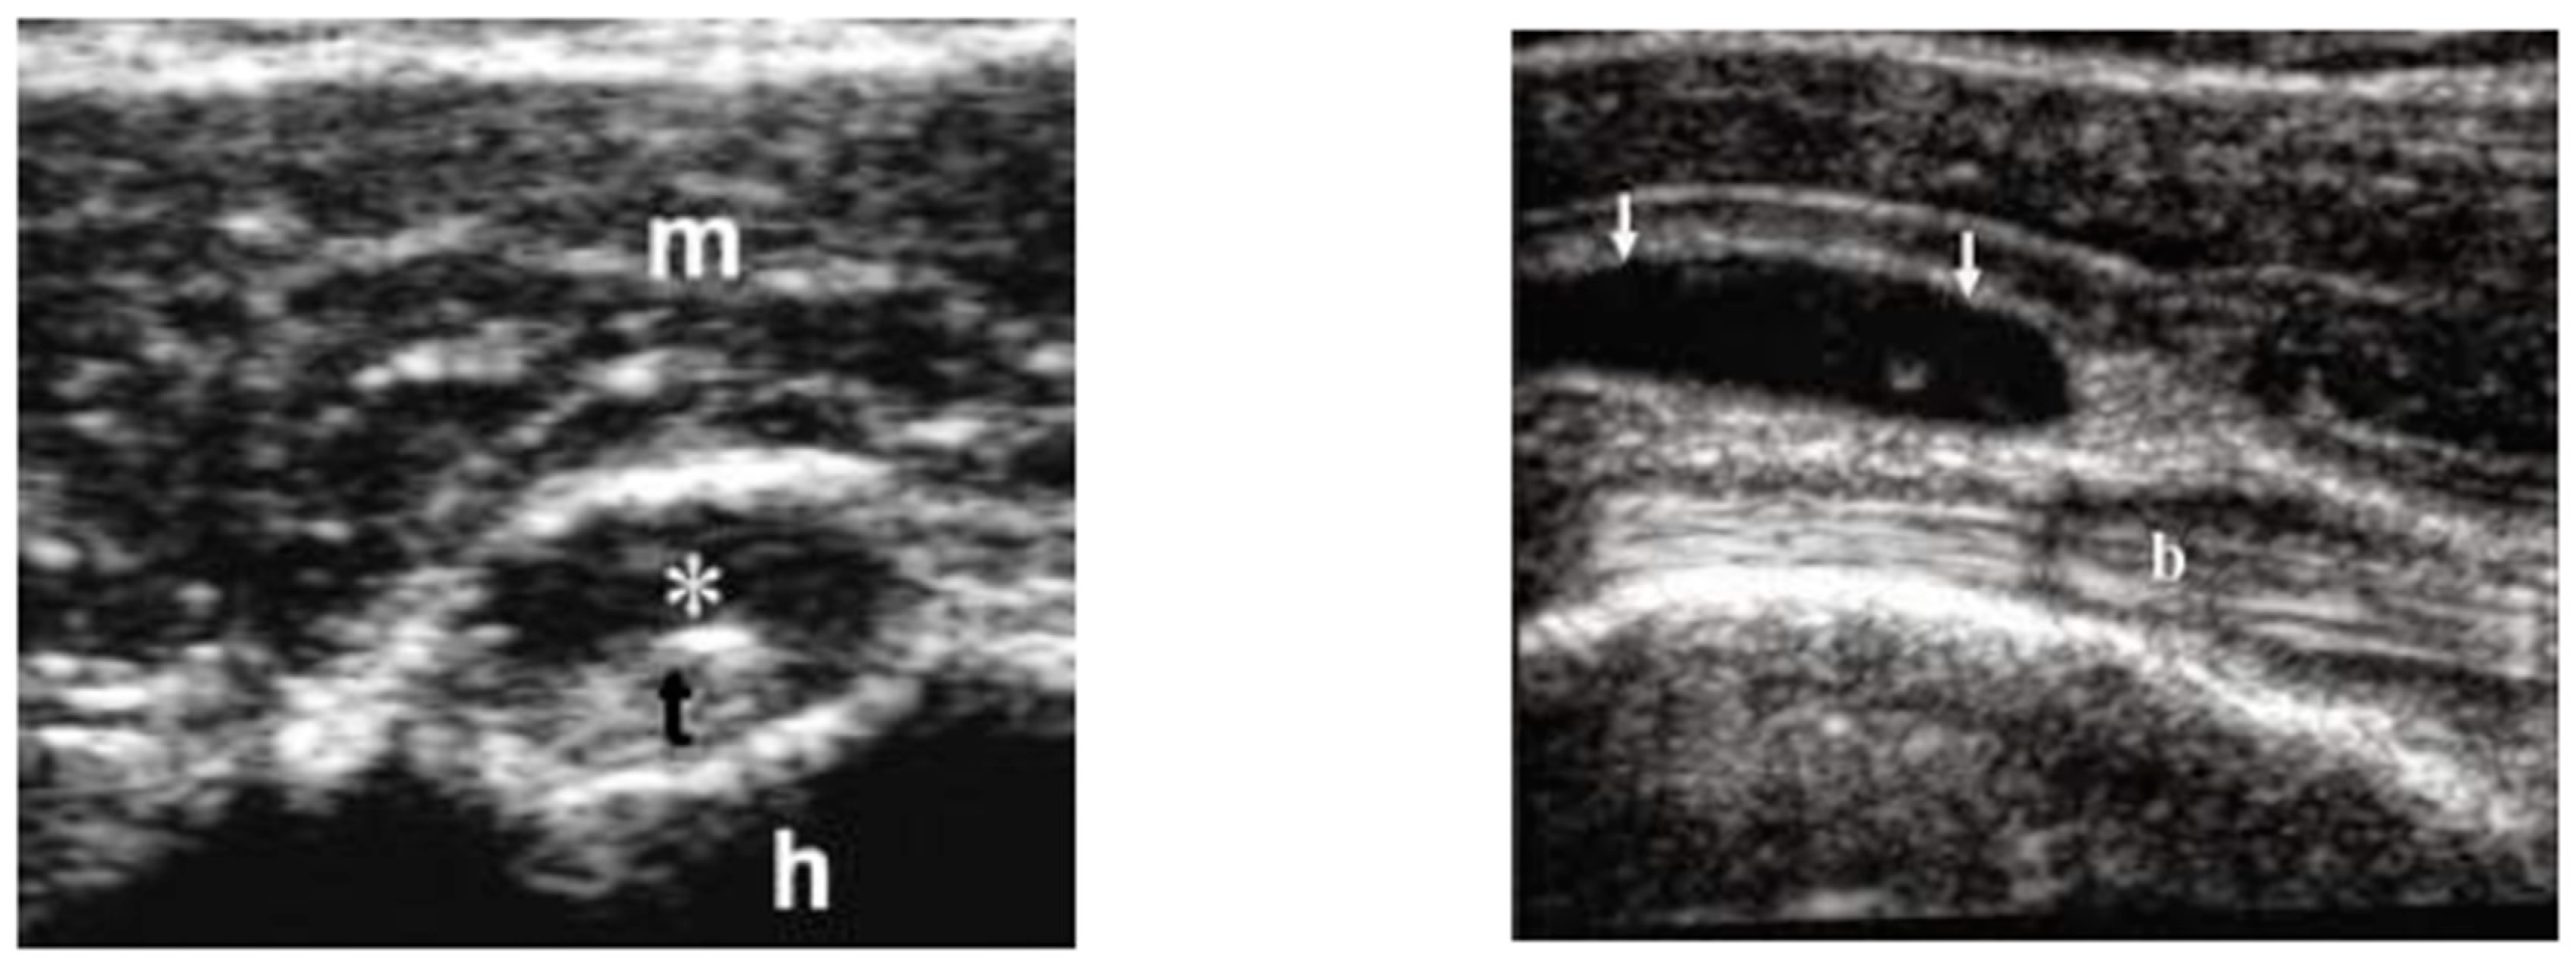

In May 2015, a 100-year-old Caucasian man was referred to our outpatient clinic complaining of chronic pain in shoulder and hip girdle pain with 4-h morning stiffness. Constitutional manifestations were not present. In the previous four months, several non-steroid anti-inflammatory drugs (NSAIDs) and painkillers associated with physiotherapy treatments gave no significant improvement in pain and self-care. He had an X-ray of the chest, shoulders and pelvic, revealing no pathologic findings. An abdominal ultrasound (US) showed mild hepatomegaly and renal cysts. He did not suffer from psoriasis; no ocular, intestinal or uninary manifestations were present. ESR was 21 mm/1st hour (normal values < 30) at the onset and 12 mm/1st hour at the time of our examination. C-reactive protein (CRP) was 4 and 3 mg/dL (normal values < 6), respectively. Other laboratory data were all negative. In particular, serum fibrinogen levels were equal to 350 mg/dL (normal values < 400 mg/dL); rheumatoid factor (RF) and anti-protein citrullinated antibodies (APCA) were in their normal range; hemoglobin was equal to 12.8 gr/dL (normal values > 12.0 gr/dL); transaminases, creatine phospho kinase (CPK), protein electrophoresis, antinuclear cytoplasmic antibodies (ANCA) were in their normal ranges. Occult blood research in the stool was negative and fecal calprotectin dosage was in the normal range. Antibodies to hepatitis C virus and Australia antigen were absent. An US examination showed bilateral long-head-biceps exudative tenosynovitis and subdeltoid bursitis in his shoulders (Figure 1) and trochanteric bursitis in his right hip. An 18-fluorodeoxyglucose positron emission tomography (18-FDG PET) associated with total body computed tomography (CT) was performed (Figure 2) and excluded pathological findings in other sites. PMR was proposed. He started with 12.5 mg/day prednisone and there was a rapid improvement. After 10 days, he spontaneously stopped prednisone, but after 24 h, the manifestations reappeared, and he took it again. Prednisone tapering was made according to the schedule proposed by an international collaborative initiative [10] and stopped after 10 months. The patient refused a control PET/CT. A new US evaluation of shoulders and hips, performed after three months, showed normal findings. During a 3-year follow-up, he never had constitutional manifestations; no clinical manifestations suggestive for an overlapping giant cell arteritis (GCA) were observed; no alternative diagnosis was possible. As for today, our patient is fine.

Figure 1.

Long-head-biceps exudative tenosynovitis (left, *) and subdeltoid bursitis (right, arrows). m is for muscle; t is for long-head biceps tendon; h is for head (omeral head); b is for bursa.